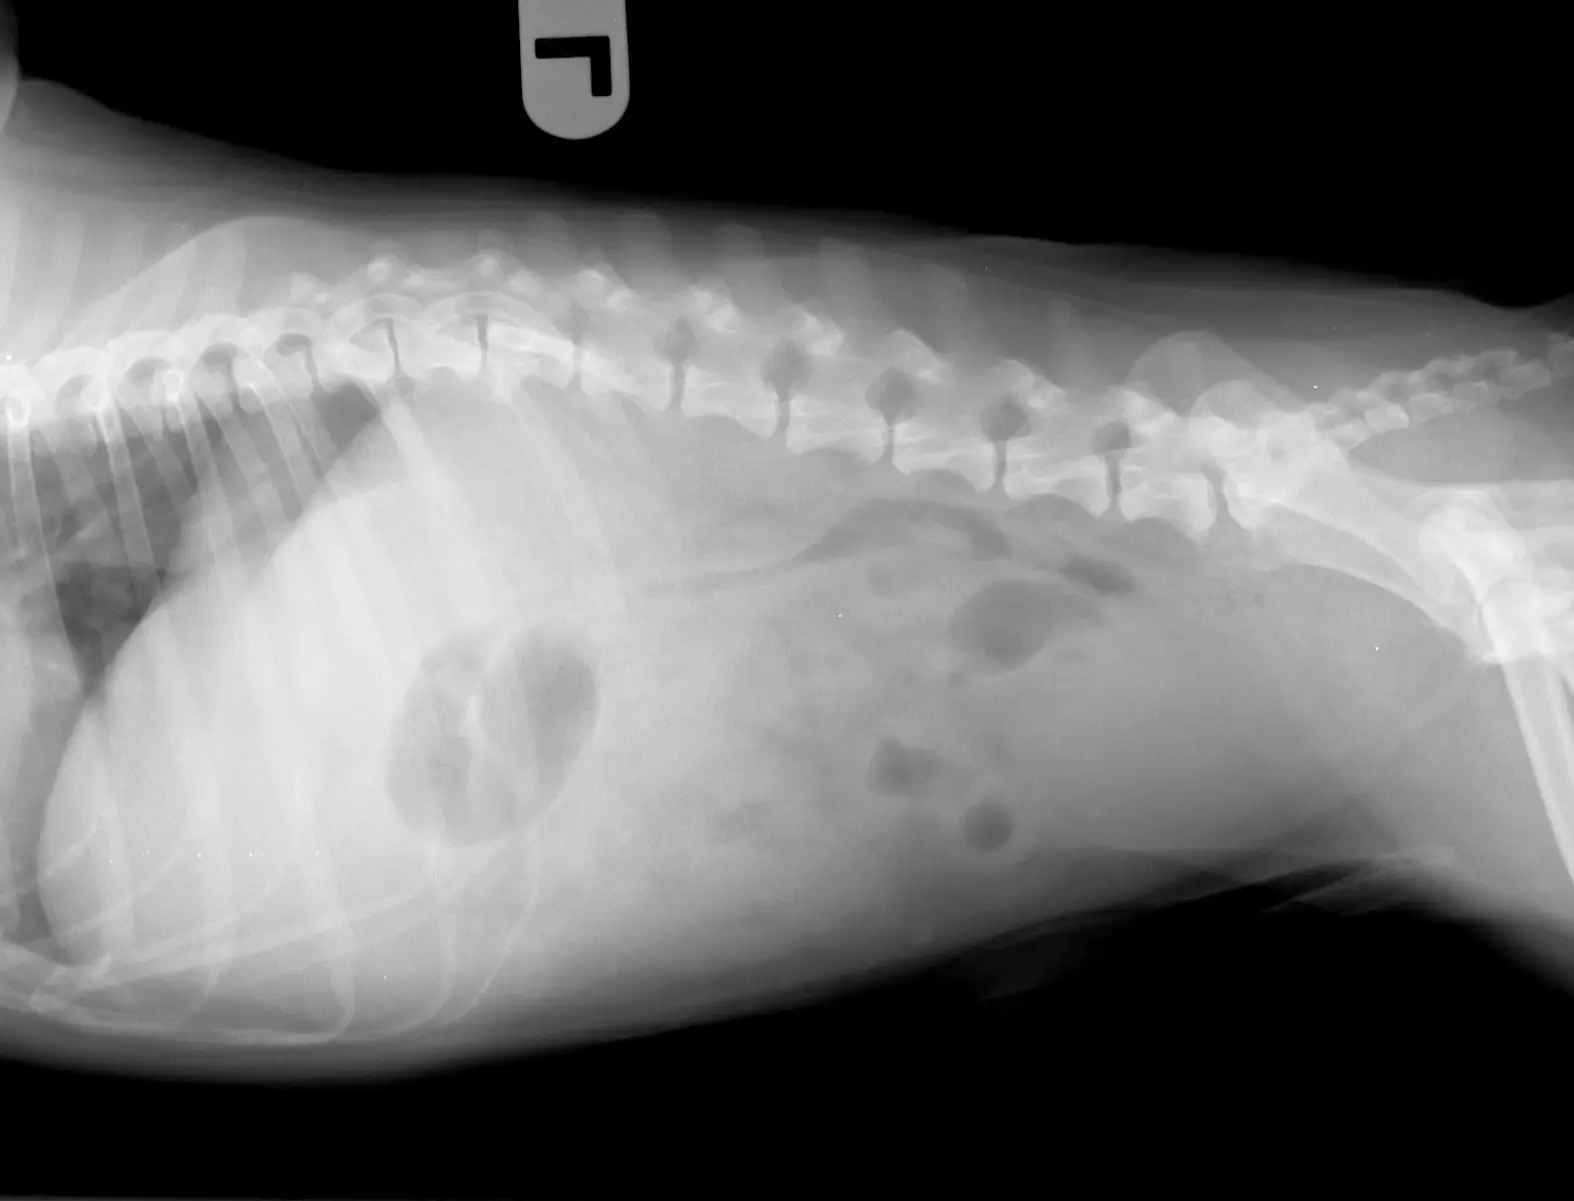

画像検査

X線検査では腹部臓器の大きさや形、位置の変化などを評価します。超音波検査では無麻酔で腹部臓器の詳細な評価が可能です。